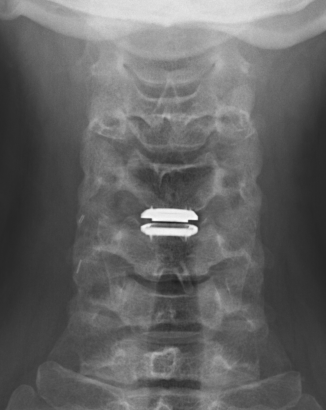

Disc replacement

Advantage

Theoretically maintain some motion and preserve other disc segments

Technique

Depuy Discover Medtronic Prestige

- anterior displacement

- posterior displacement and spinal cord injury

- subsidence 3% - higher risk if remove or disrupt end plates

- osteolysis

- implant failure

- heterotopic ossification